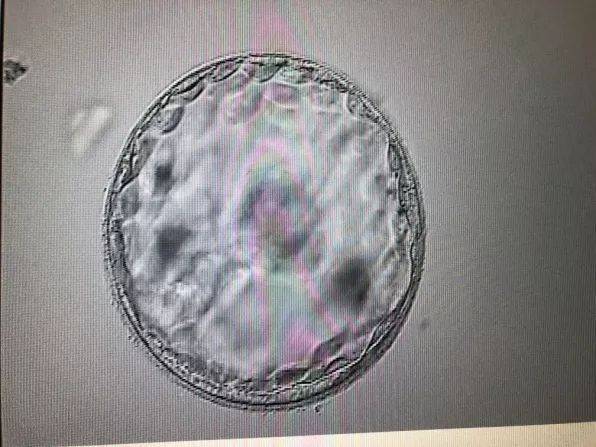

- 移植囊胚几天能测出怀孕 移植囊胚几天能测出怀孕图片05-24